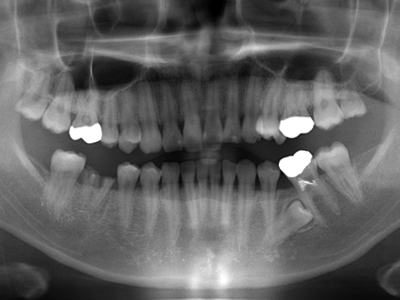

1. 初診時X線パノラマ

平成19年の年末に初めて来院した時のX線パノラマです。主訴が右下6番の銀歯の脱離との事ですが、同部はもう残根となり抜歯必至です。他には上顎親知らず。左上4番の転位歯、左下5番の埋伏と6番の不良根充が目立ちます。